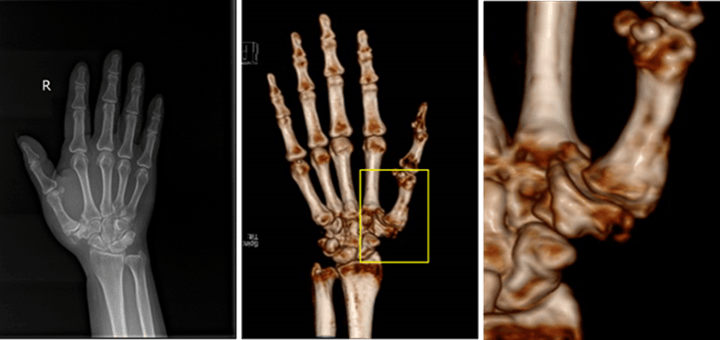

3D打印多孔鉭金屬掌指關(guān)節(jié)置換成功實(shí)施

患者于阿姨(化名),多年來一直受到右手疼痛的困擾,就診于多家醫(yī)院均診斷為右手第一掌指關(guān)節(jié)炎,關(guān)節(jié)面受累明顯,掌指關(guān)節(jié)半脫位,接受了包括口服藥、敷藥、注射等多種療法都無明顯效果,活動明顯受限,而且關(guān)節(jié)疼痛難耐,生活質(zhì)量受到嚴(yán)重影響。